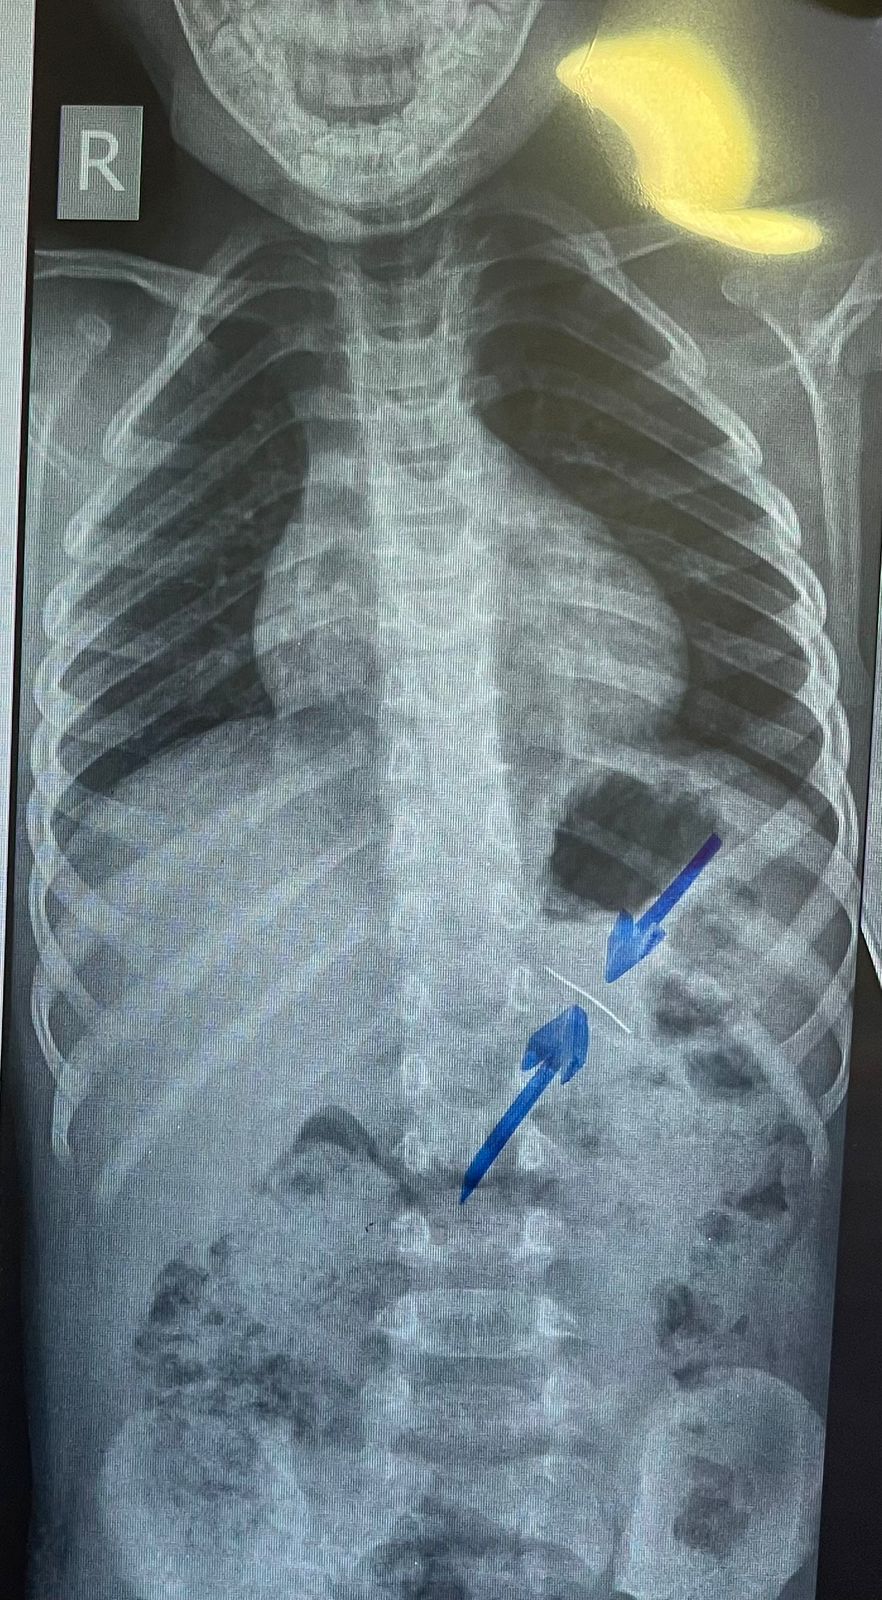

نجح فريق طبي من وحدة أمراض الجهاز الهضمي والكبد ومناظير الأطفال بقسم طب الأطفال بـ مستشفى سوهاج الجامعي في إجراء تدخل دقيق لاستخراج دبوس من معدة طفل عمره 4 سنوات، بإستخدام منظار معدة خاص بالأطفال، دون حدوث أي مضاعفات، وقد غادر الطفل المستشفى بعد ثلاث ساعات فقط من الإجراء، وهو في حالة صحية جيدة.

وأكد الدكتور أحمد كمال، المدير التنفيذي للمستشفيات الجامعية، أن التعامل مع الحالة تم بسرعة وكفاءة، حيث تمكن الفريق الطبي بـ مستشفى سوهاج الجامعي من استخدام المنظار الخاص بالأطفال لاستخراج الدبوس دون أي تدخل جراحي، مما ساهم في خروج الطفل من المستشفى في نفس اليوم بحالة ممتازة.